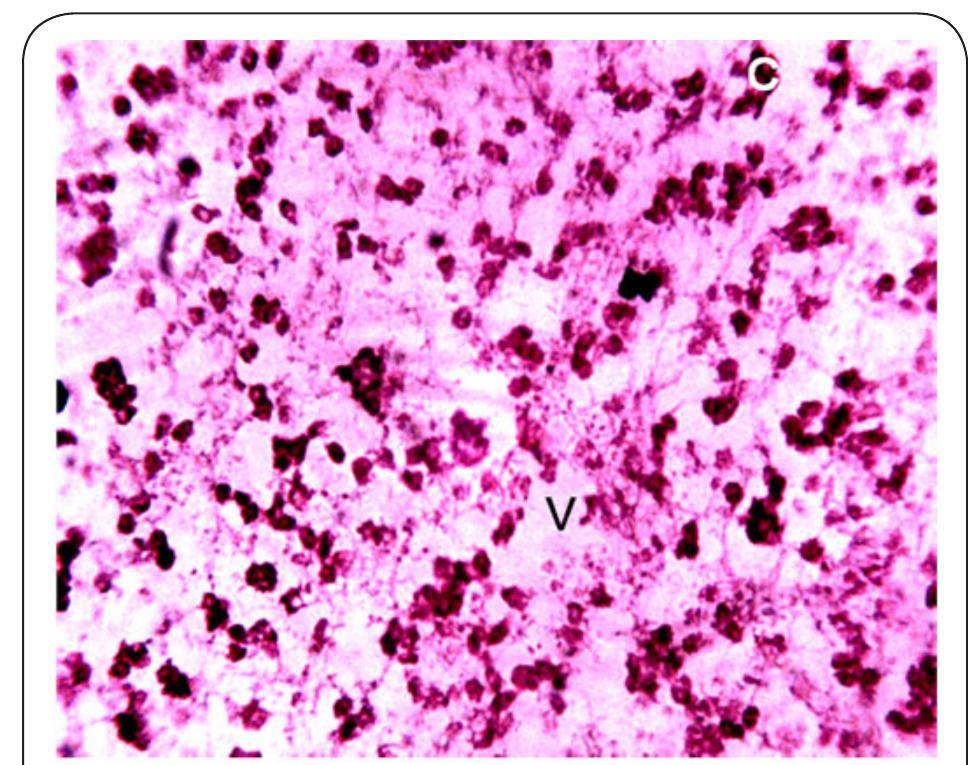

Dr. Ozovehe Patrick Samuel - FEDERAL UNIVERSITY OF TECHNOLOGY, MINNA-NIGERIA